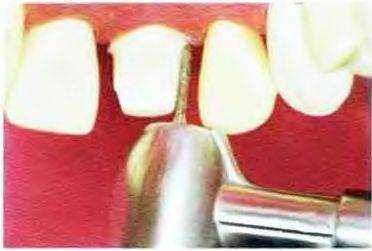

Рис. 13-10. На втором этапе бор ориентируют параллельно придесневой части вестибулярной.

Рис. 13-11. Бор погружают по средней линии параллельно придесневой трети вестибулярной поверхности зуба Следует убедиться в полном погружении бора или даже глубже. В апикальном направлении кончик бора не должен проникать под десну, даже если планируется расположение края реставрации на уровне десны или апикальнее. Необходимо создавать, как минимум, еще две подобные проточки в области углов коронки зуба.